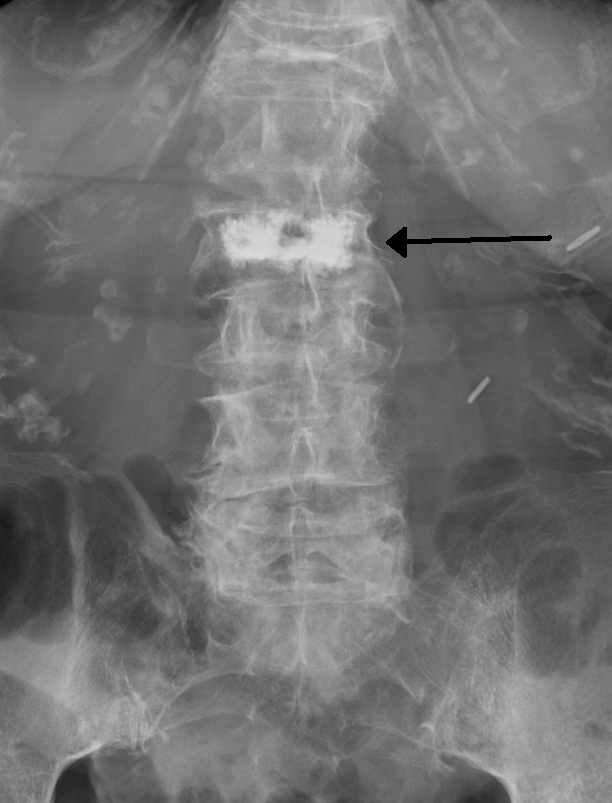

骨質疏鬆症可謂「隱形殺手」,剛開始,患者大多只覺身高縮水,並不易察覺;但隨著骨質流失到一定程度,骨頭卻可能碰到輕微外力就應聲斷裂,嚴重者,可能連咳嗽、搬東西都成了危險動作。

骨折代價之沈重不在話下,吳凱文主任更指出,因患者本身骨質不佳,加上輕忽骨鬆威脅等因素,都使得曾發生嚴重骨折的患者五年內再次骨折的比率高達30%,因此「初期目標是降低患者再次骨折的發生,更好就是預防勝於治療,連第一次的骨折都不要有,是最好的狀況。」